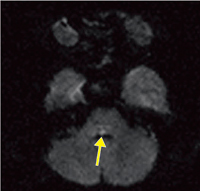

■症例3:脳幹梗塞

70歳,女性。複視を訴えて来院。他覚的に左眼球の内転障害,右眼球の水平方向の運動障害,輻輳正常,軽度の右顔面神経麻痺を認めた。拡散強調画像にて橋脳背側,第四脳室に接するやや右側にhigh intensity spot(↑)を認める。 DWI,FOV:280mm,TR/TE:11295/126.6,FA:90°,スライス厚:5.0mm